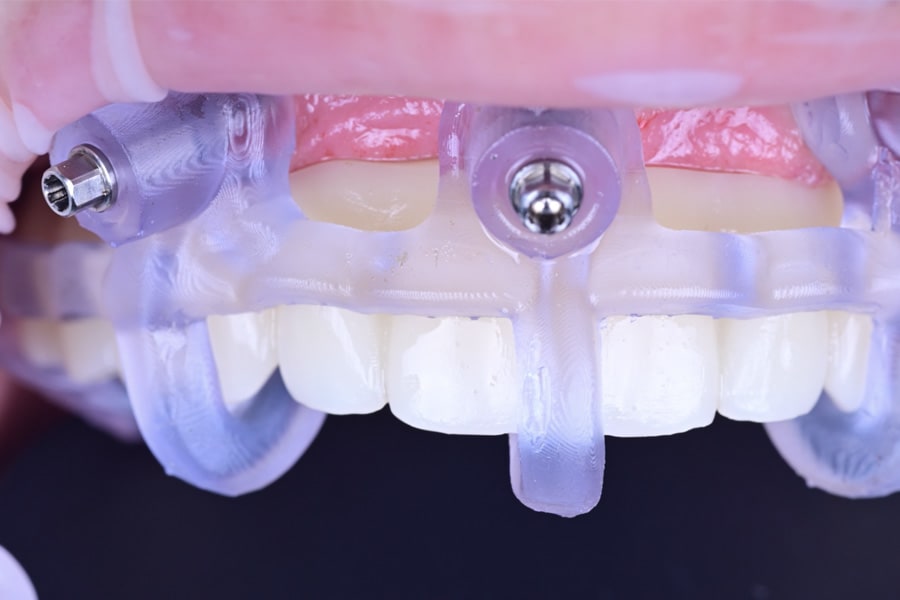

At the definitive phase, scan bodies were connected, and digital impressions were made. A passive-fit verification jig was fabricated by splinting implant analogs with resin, then sectioning and re-luting to relieve shrinkage stress (Figure 21). The jig confirmed accuracy intraorally and on the master model, ensuring a strain-free framework.

Definitive frameworks were CAD-designed and CNC-milled from titanium alloy (Figure 22). Clinical fit was confirmed with the Sheffield test (Figure 23). Monolithic zirconia superstructures were produced and vestibularly veneered with feldspathic ceramics to enhance translucency and texture (Figure 24 and Figure 25). Selective pink ceramic was applied in gingival areas requiring soft-tissue compensation (Figure 26 and Figure 27).